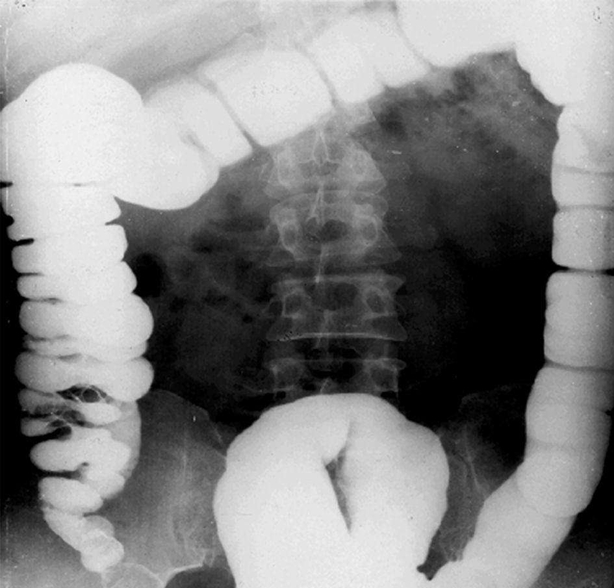

腸梗阻常見原因:動(dòng)力性、麻痹性、痙攣性: 機(jī)械性(最為常見)、單純性(無血運(yùn)障礙)、絞窄性(有血運(yùn)障礙)、血運(yùn)性(腸系膜動(dòng)脈血栓)。

急性小腸梗阻:小腸擴(kuò)張積氣,小腸腔內(nèi)積液,結(jié)腸內(nèi)氣體少。